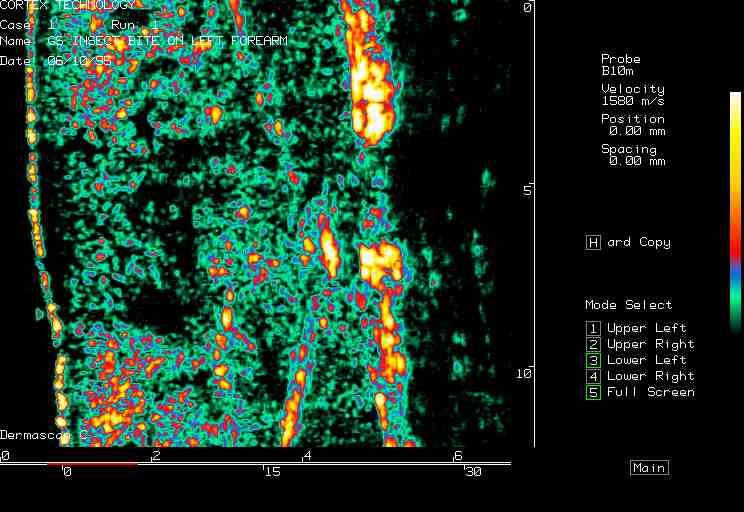

20 MHz 2D images

| Reactions |  Irritant reaction |

Insect bite |